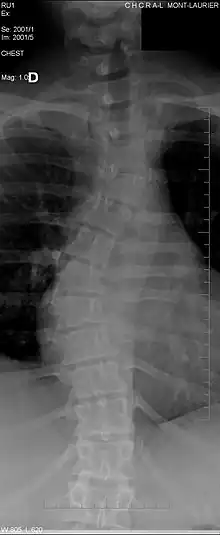

La scoliose

Même si elle ne cause pas forcément des douleurs chez les patients, elle reste responsable de certaines douleurs chroniques. Elle entraîne des troubles morphologiques de la colonne vertébrale et des disques intervertébraux. Par exemple, les patients atteints de scoliose ont souvent des dépôts de calcium (calcification ectopique) dans les cartilages périphériques et parfois dans le disque lui-même[11]. En plus de la scoliose, qui courbe latéralement la colonne vertébrale en " S ", les vertèbres peuvent également présenter des anomalies entraînant une cyphose (bossu) lié avec l'âge, ou une lordose (creux) qui est souvent liée à la grossesse ou l'obésité.

Trouble de l'espace entre deux vertèbres

Un trouble de l'espace entre deux vertèbres est généralement détecté par rayons X et caractérise un espace anormal entre deux vertèbres. Chez les patients sains cet espace correspond à l'épaisseur d'un disque intervertébral sain, mais il peut devenir plus élevé dans des cas pathologiques (cas de spondylodiscite avec infection du disque intervertébral)[12].